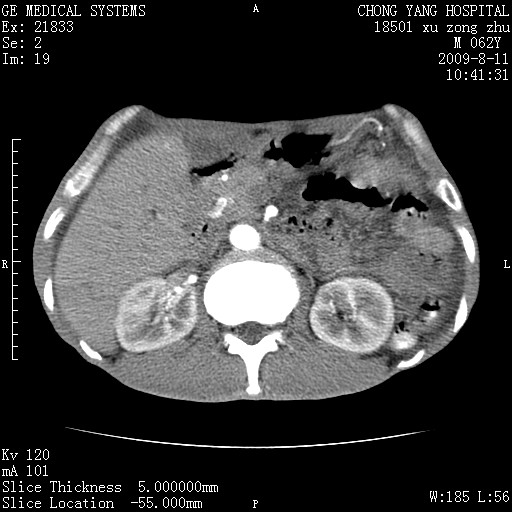

以下是引用杀毒软件在2009-8-11 16:35:00的发言:[br]肝内胆管扩张局限于左叶,胆管内有结石伴肝外胆管结石,胆管壁增厚呈弥漫性并发腹腔积液,胰腺边界模糊。[br][br]考虑---胆总管及肝内胆管结石继发胆管炎及胰腺炎,左肾下极囊肿,腹水。

以下是引用zjzjr在2009-8-11 17:35:00的发言:[br]肝内胆管扩张局限于左叶,胆管内有结石伴肝外胆管结石,胆管壁增厚呈弥漫性并发腹腔积液。[br][br]考虑---胆总管及肝内胆管结石继发胆管炎,左肾下极囊肿,腹水。